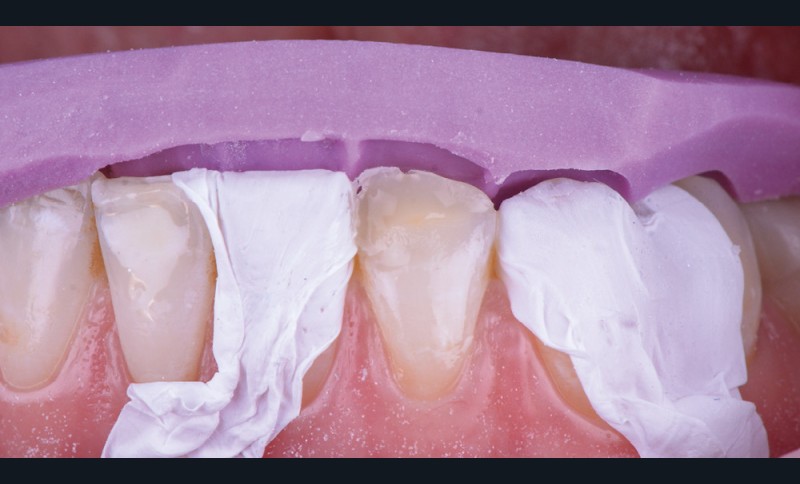

2. Wax up

Le wax-up est réalisé au laboratoire par le prothésiste (fig. 2). Il permettra de reproduire l’anatomie de la ou des dents concernées. Il est préférable de ne pas ajouter de cire dans la partie la plus cervicale de la dent afin d’éviter toute fusée de matériau composite lors de l’injection. Par ailleurs, la clé s’appuyant sur la partie gingivale, il est possible de gratter le plâtre d’un dixième de millimètre dans la zone du sulcus et sur la gencive. Cela permet de compenser la dépressibilité des tissus mous (fig. 3).